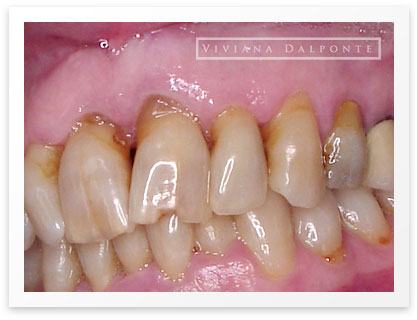

CASO 6: Restauración con prótesis fija en ambos maxilares